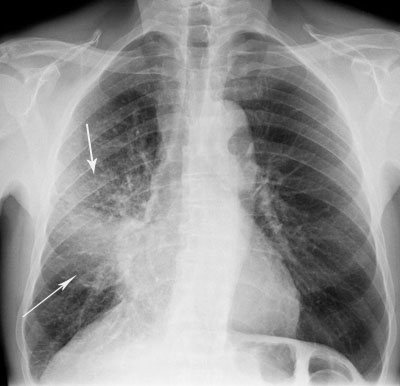

Oamenii de ştiinţă din Statele Unite au descoperit că riscul de a face pneumonie este de 100 de ori mai mare la persoanele infectate cu gripă, relatează un articol din revista Science Translational Medicine.

"Legătura dintre gripă și pneumonia pneumococică este prezentată clar în studiul nostru. Pe scurt, analiza noastră a relevat o influenţă de scurtă durată, dar semnificativă - creşterea de 100 de ori a riscului îmbolnăvirii de pneumonie pneumococică după o infecţie gripală, "- a declarat autorul principal al studiului Pezhman Rohani de la Universitatea din Michigan.

Anterior, relația dintre gripă și pneumonie a putut fi stabilită numai la animale. Rohani şi colegii săi au creat un model pe calculator de răspândire a pneumoniei bacteriene la om pentru a testa diferite ipoteze care descriu rolul gripei în acest proces. Oamenii de ştiinţă au evaluat conformitatea fiecărei ipoteze cu rapoartele epidemiologice pe parcursul a 20 de ani între 1989-2009, în care săptămânal erau înregistrate cazurile de spitalizare pe motiv de gripă şi pneumonie în Illinois.

Aceste observații confirmă ipoteza că sensibilitatea crescută a pacienților cu gripă la agenții patogeni ai pneumoniei durează timp de 5-7 zile de la infectare. Oamenii de ştiinţă au descoperit, de asemenea că, în perioada de vârf a sezonului epidemic - gripa a fost cauza a 40% din cazuri de pneumonie, iar media anuală a aceastei valori nu depășește 10%. Poate că acesta este motivul din care cercetările anterioare nu au reușit să demonstreze o relație între cele două boli. Fiți cu noi pe facebook: